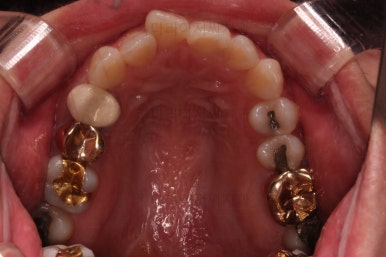

오늘 부산부분치아교정 키다리아저씨치과에서 소개해 드릴 환자분은 앞니가 삐뚤고, 토끼처럼 나와있다고 교정치료를 원하셨던 분입니다.

웃을 때 모습에서 앞니가 조금 삐뚤어 미적으로 좋지 못하고, 특히나 대문니가 더 튀어나와 강조되어 보이고 유달리 커보이는 효과까지 주네요.

어금니의 맞물린은 100점은 아니지만 생활하기에 크게 나빠보이지 않고요.

특히 임플란트도 있는 상황이었기 때문에 굳이 어금니까지 교정할 필요는 없어보였어요.

앞니 부분교정으로 치료계획을 세웠는데 다른 분들에 비해 난이도가 높은 치료가 예상되었던 이유는 우측 상단의 사진에 선 그어놓은 부분을 보시면 어금니에 비해 아래앞니가 약간 솟구쳐 높이가 맞지 않다는 점이었어요.